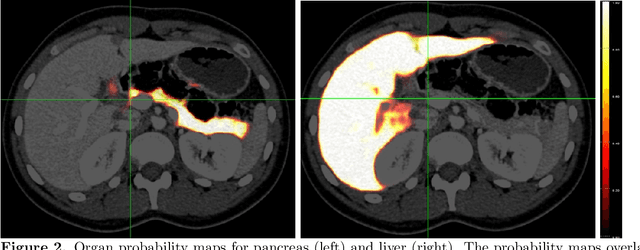

Abstract:Human body is a complex dynamic system composed of various sub-dynamic parts. Especially, thoracic and abdominal organs have complex internal shape variations with different frequencies by various reasons such as respiration with fast motion and peristalsis with slower motion. CT protocols for abdominal lesions are multi-phase scans for various tumor detection to use different vascular contrast, however, they are not aligned well enough to visually check the same area. In this paper, we propose a time-efficient and accurate deformable registration algorithm for multi-phase CT scans considering abdominal organ motions, which can be applied for differentiable or non-differentiable motions of abdominal organs. Experimental results shows the registration accuracy as 0.85 +/- 0.45mm (mean +/- STD) for pancreas within 1 minute for the whole abdominal region.